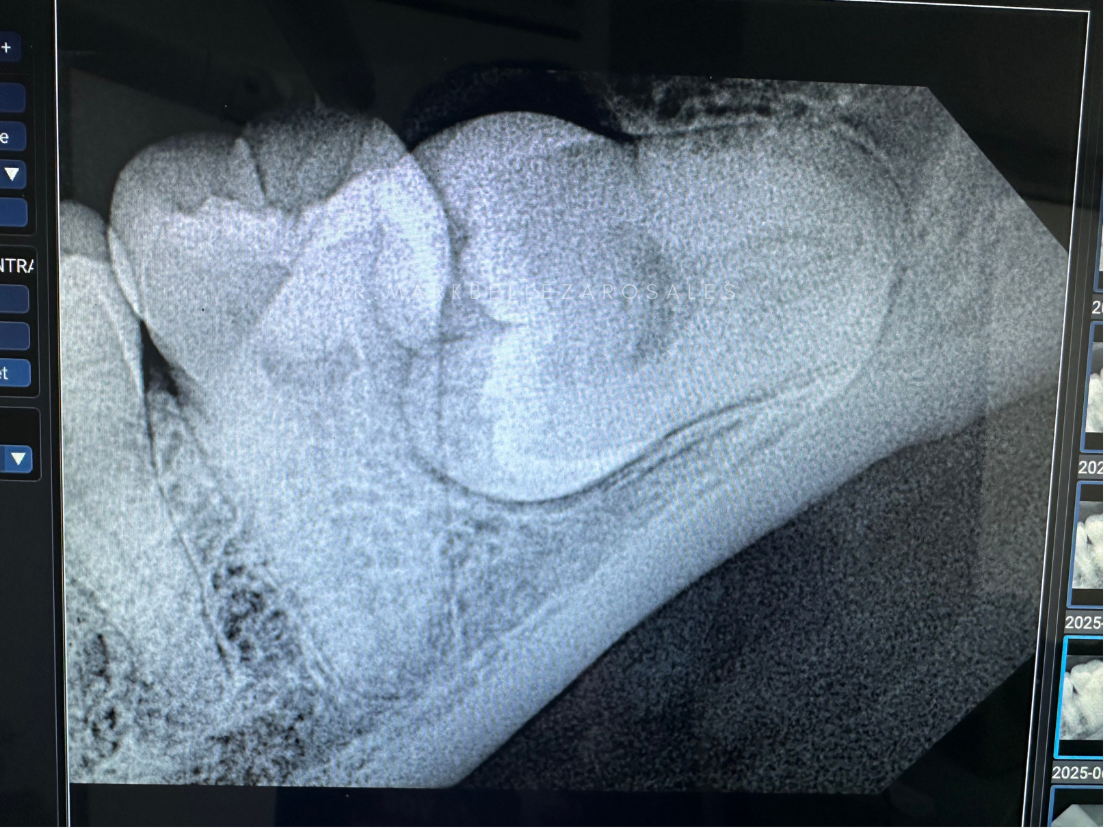

Wisdom tooth removal is a dental procedure performed to extract one or more third molars that may be impacted, painful, or causing crowding and infection. The procedure helps prevent future dental problems and relieves discomfort while protecting overall oral health.